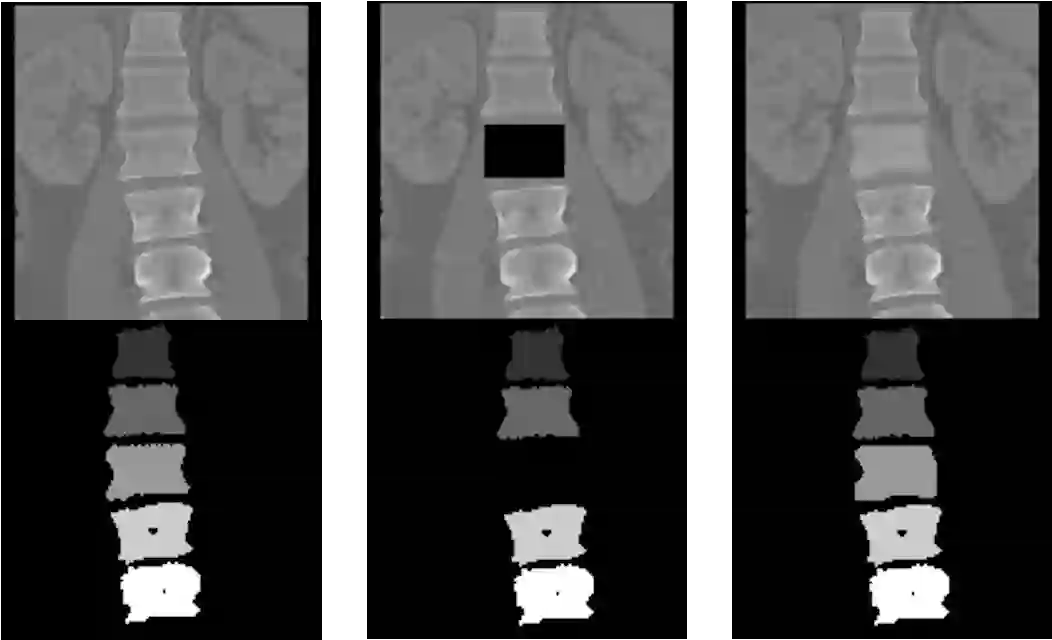

Symptomatic spinal vertebral compression fractures (VCFs) often require osteoplasty treatment. A cement-like material is injected into the bone to stabilize the fracture, restore the vertebral body height and alleviate pain. Leakage is a common complication and may occur due to too much cement being injected. In this work, we propose an automated patient-specific framework that can allow physicians to calculate an upper bound of cement for the injection and estimate the optimal outcome of osteoplasty. The framework uses the patient CT scan and the fractured vertebra label to build a virtual healthy spine using a high-level approach. Firstly, the fractured spine is segmented with a three-step Convolution Neural Network (CNN) architecture. Next, a per-vertebra rigid registration to a healthy spine atlas restores its curvature. Finally, a GAN-based inpainting approach replaces the fractured vertebra with an estimation of its original shape. Based on this outcome, we then estimate the maximum amount of bone cement for injection. We evaluate our framework by comparing the virtual vertebrae volumes of ten patients to their healthy equivalent and report an average error of 3.88$\pm$7.63\%. The presented pipeline offers a first approach to a personalized automatic high-level framework for planning osteoplasty procedures.